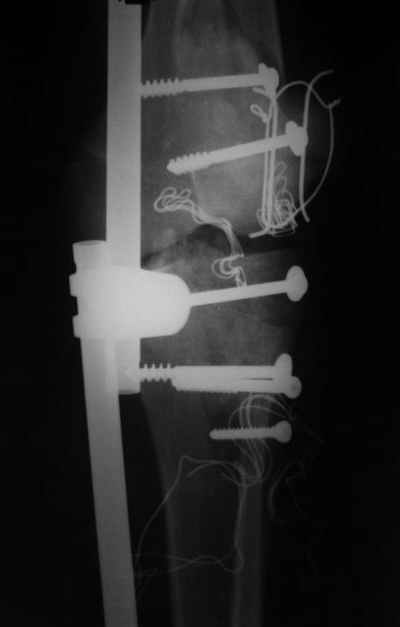

На снимке № 1 вид раны,

№2 покрытие губкой,

№3 финальное закрытие пленкой и после включения вакуума,

№4 снимок через два дня после операции, супракондилярный перелом, при поступлении конечность была холодная и без пульса, подозрение на повреждение сосудов, сделана ABI (ankle-brachial index) в приемном отделении, индекс меньше 1 к 0.9 в норме 1 к 1.1, срочная ангиография в операционной после Ex-Fix, по два стержня в сегменте наложен в течение 20 мин, повреждение подколенной артерии, ушивание сосудистым хирургом через медиальный доступ в дистальном отделе бедра и двухразрезная профилактическая фацсиотомия, перкутанная фиксация каннюлированными шурупами несмещенного перелома шейки бедра и дополнительные стержни в фиксаторе для жесткости.